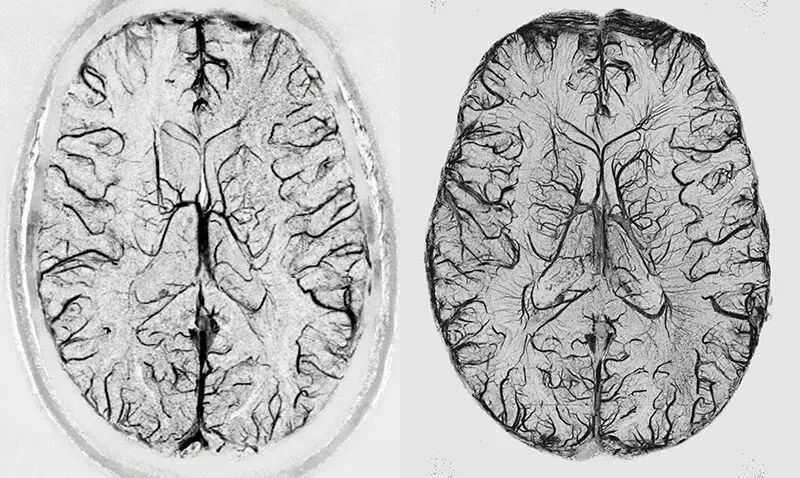

对比来说,在3T时,MRI可以解析小至1毫米的大脑细节;7T时,分辨率可以精确到0.5毫米,足以识别人类大脑皮层内的功能单元,或许还能看到信息如何在人脑中的神经元集合之间流动;而具有更高场强度的MRI预计将具有至少两倍于7T仪器的分辨率。

普通 3T MRI扫描(左)统与德国马克斯普朗克研究所的9.4TMRI扫描(右)统一大脑断面的效果——显然右边9.4T的机器扫出来细节丰满得多。

Credit:Rolf Pohmann/Max-Planck-Institute for Biological Cybernetics